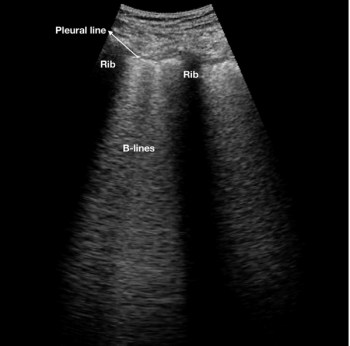

Lung ultrasound scans pinpoint lingering lung damage in patients who meet clinical parameters for hospital discharge, alerting doctors to patients who will need longer-term care.

Images demonstrate high accuracy for identifying B-lines, thickened pleural lines, and pulmonary consolidation features.